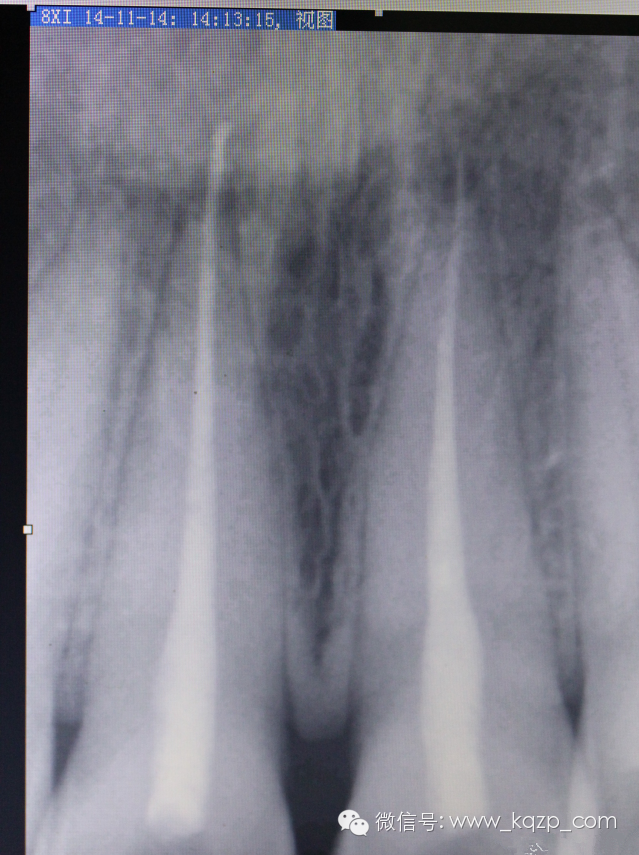

拍片見35根管治療后超充。

約診拆根充,看能否把超充取出,如不能取出則考慮拔牙或者根尖手術(shù)。

拍片,

順手把工作長(zhǎng)度也確定下。